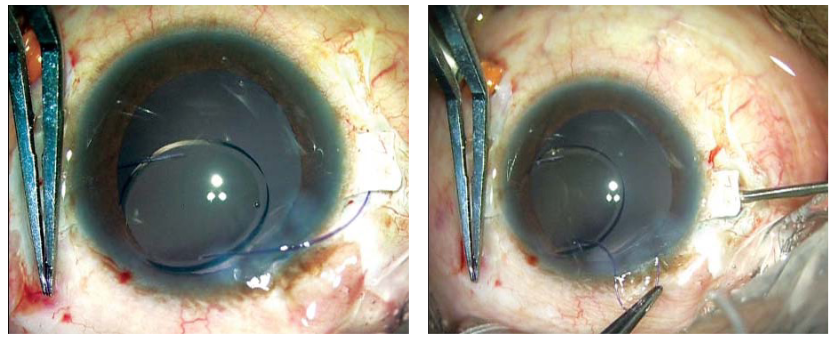

图2A和B:图示在巩膜瓣下用22G针头进行巩膜切开。用25G镊子将IOL襻暴露。